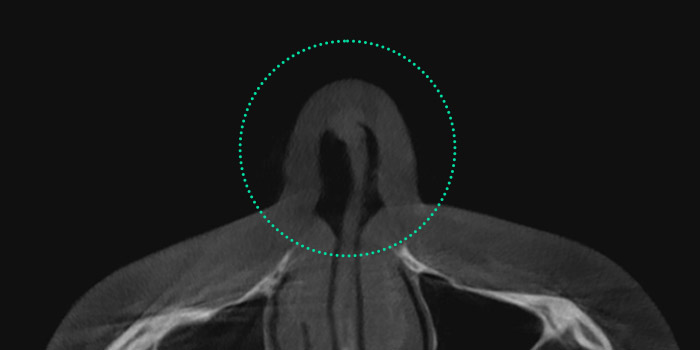

Nasal Valve Stenosis

The nasal valve, located at the upper part

of the internal nose, regulates airflow.

When the septal cartilage is bent, it narrows

this passage, resulting in breathing difficulties and

nasal obstruction. This condition, known as nasal

valve stenosis, is more common in individuals

with a low nasal bridge.

Narrowing of the upper internal nasal area,

responsible for regulating airflow, leads to nasal

obstruction and sleep disorders.